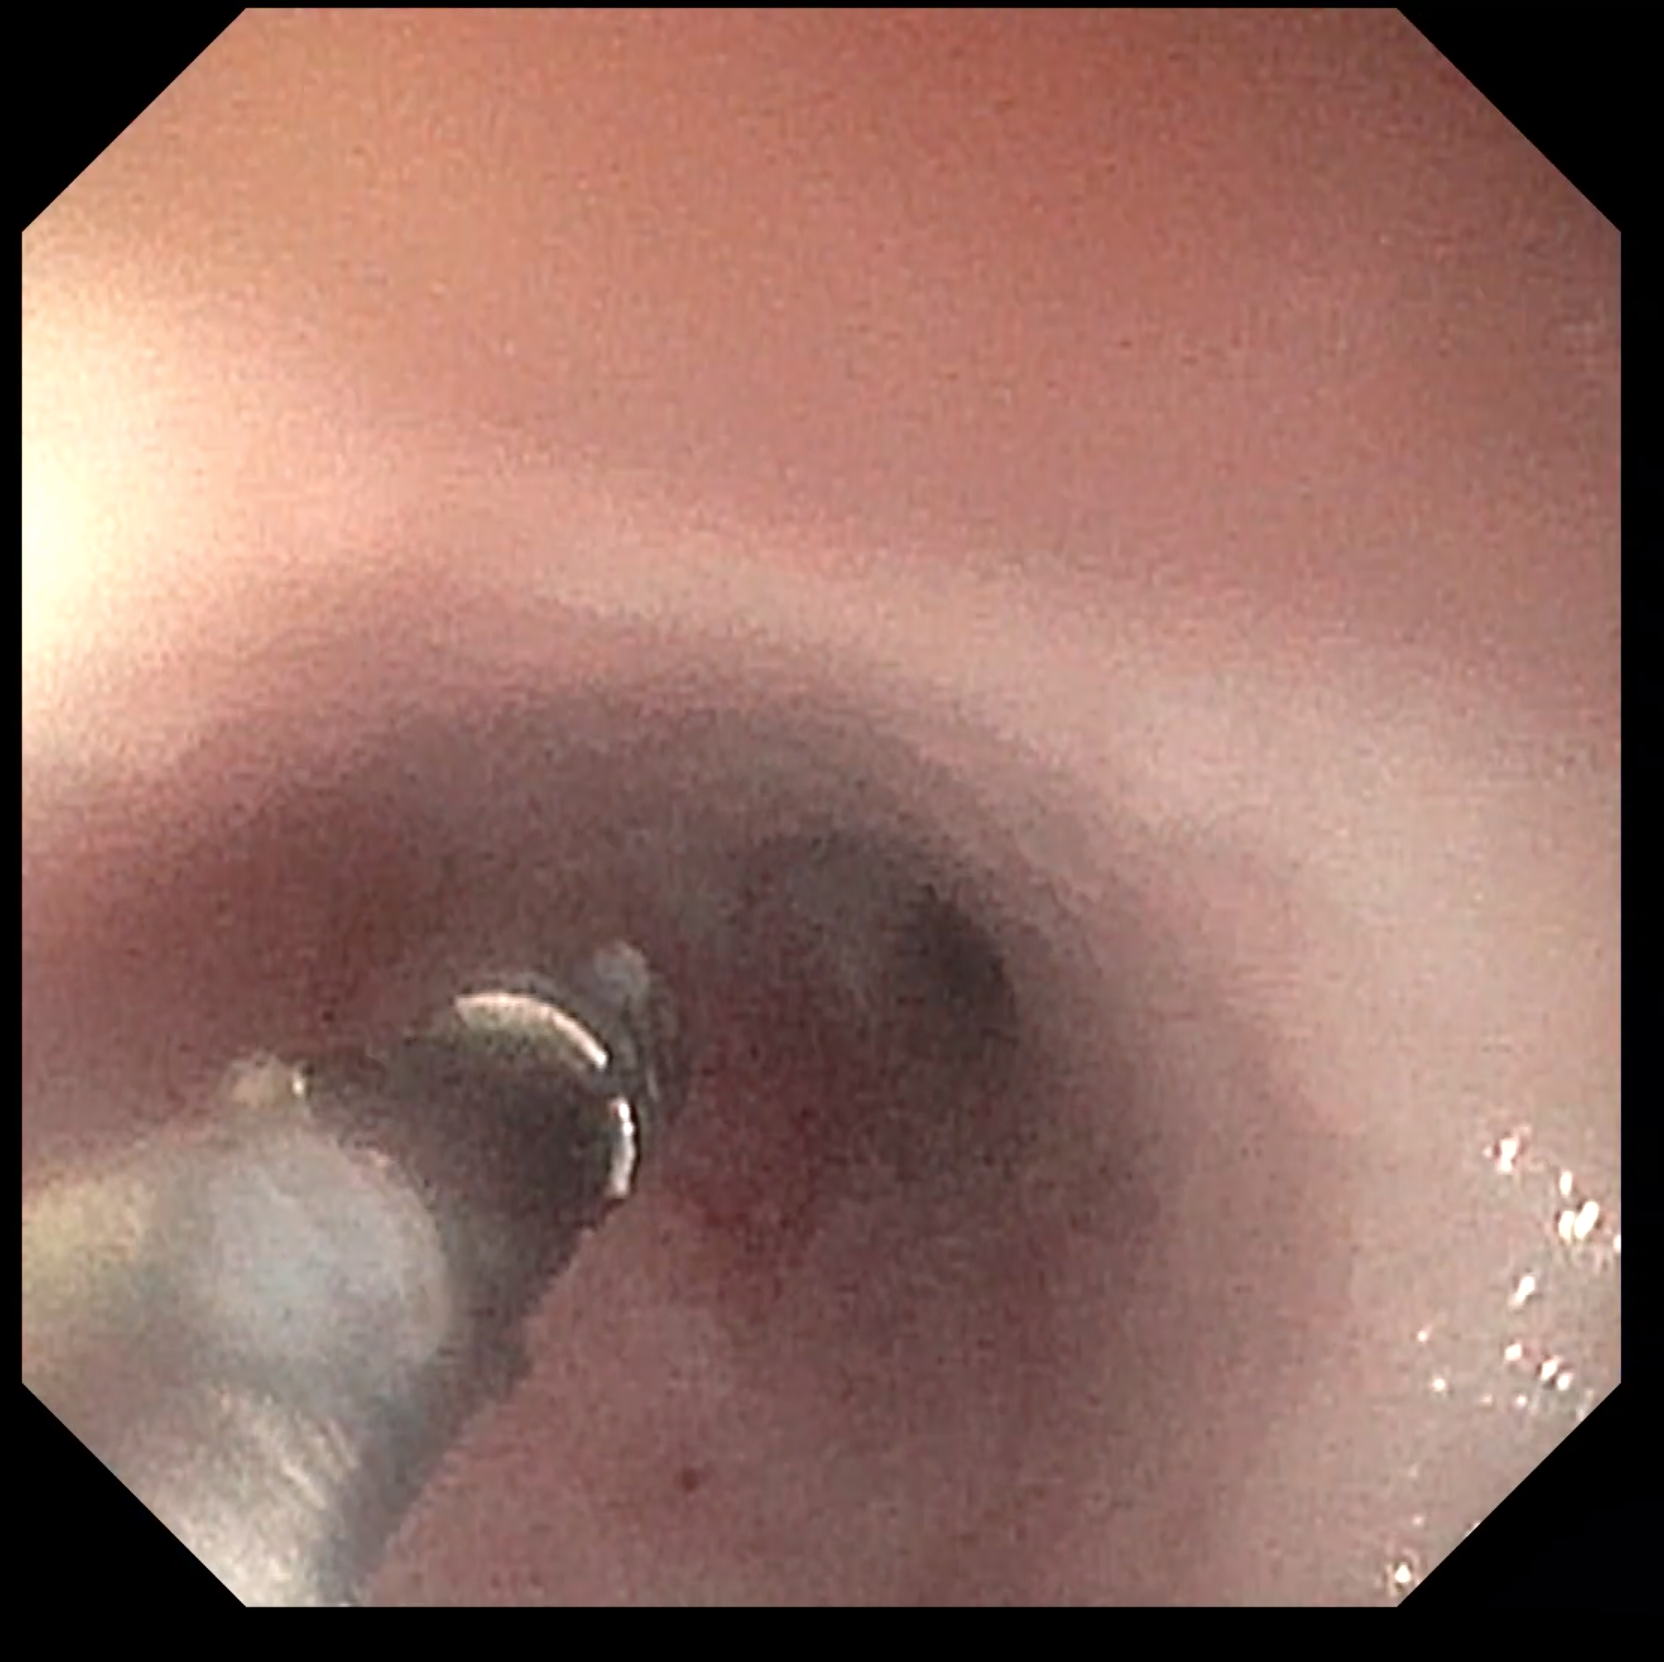

専用器具を用いて腸の生検を行っている写真です